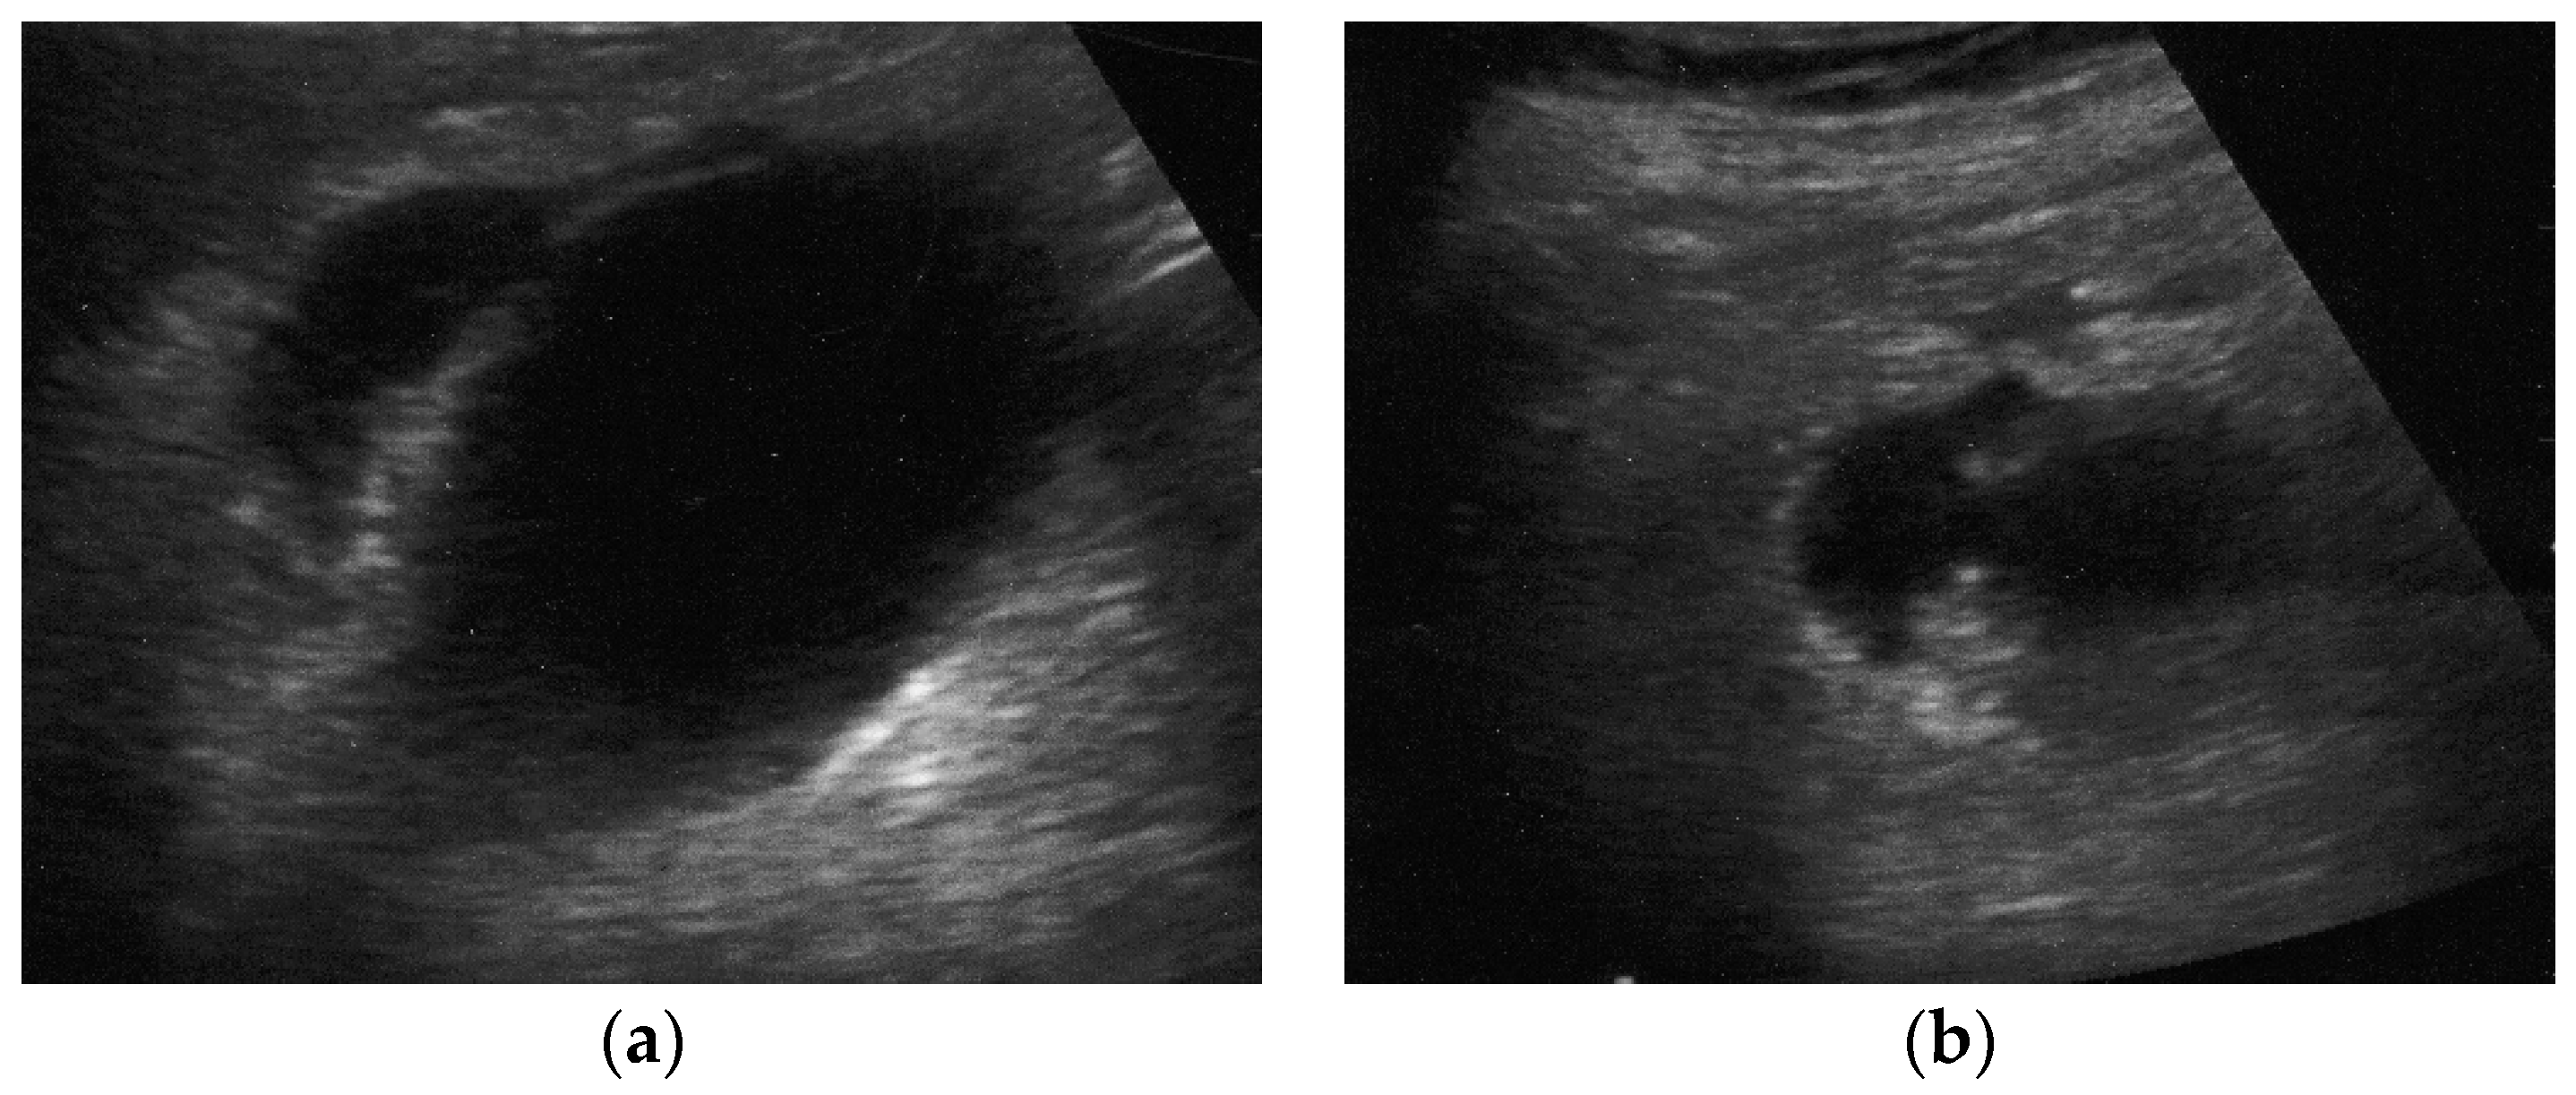

Sometimes, the adjacent liver parenchyma may show findings suggestive of diffuse edema, such as a hypoechoic aspect, possibly with prominent echogenic portal triads, known as “starry-sky” appearance (Figure 2). [29,32]

The most common sonographic finding in GC is an irregular gallbladder wall thickening,[49,50] characterized by multiple striations with alternating hypoechoic or hyperechoic bands (Figure 2). [27] This sonographic pattern is due to the presence of intramural hemorrhage or micro-abscesses. [3,44] Intraluminal membranes, formed by strands of fibrinous exudate and desquamated or “denuded” mucosa, are considered a more specific finding in GC, although less common (Figure 3).[3,44,49,50]

Typically, at US examination the gallbladder is distended and contains intraluminal echogenic material [76] without posterior acoustic shadows, lying in the dependent portion of the lumen. The echogenic material moves as the patient’s position change, usually resembling biliary sludge (Figure 2). [70] Additional sonographic findings of GE are gallbladder wall thickening and pericholecystic fluid. [76,77] Rarely, the presence of intraluminal air been reported, suggesting infection by anaerobic pathogens such as Clostridium or Bacteroides. [77]